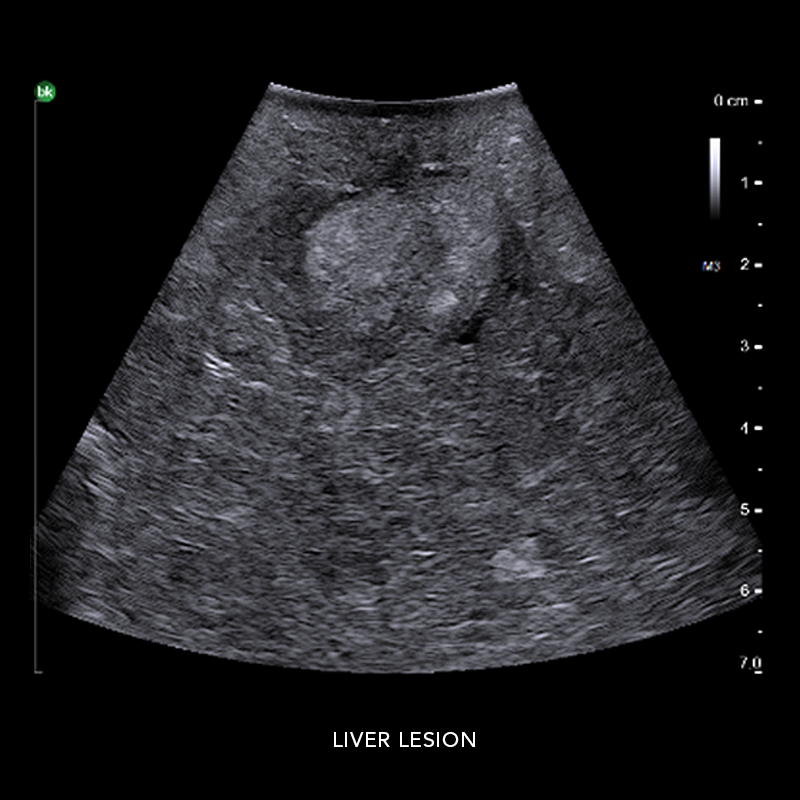

Hepatobiliary Surgery

Reach critical information and compensate for no haptic feedback with active imaging

Intraoperative ultrasound can assist in identifying 10-25% more hepatic lesions than with preoperative imaging alone.* Use intraoperative ultrasound (iUS) to support liver resections, distal pancreatectomies, and more. iUS helps to adapt surgical plans, assess progress, and perform organ-sparing procedures. The active imaging provides real-time information to understand complex anatomical variations, tumor locations, and invasion of vasculature, as well as help define an adequate margin of rection. At the end of the procedure, active imaging can provide certainty and help confirm results.